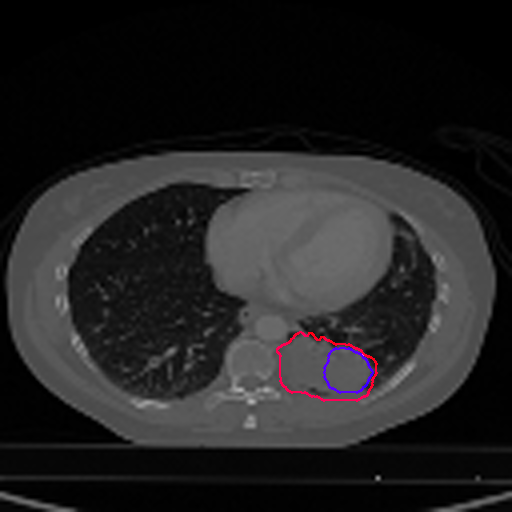

A qualitative analysis of our results reveals the strengths and weaknesses of our proposed model. In most cases, regardless of the size of the ground truth, our model predicts the tumor shapes very well. This is evident from Figure 4 where the ground truth and the prediction (by Deeply Supervised MultiResUNet) are shown in red and blue respectively. Although the tumors are in various arbitrary locations within the lung and appear in diverse sizes, the red and blue margins appear to coincide almost perfectly.

Figure 5 shows a comparison between predictions by the MultiResUNet model and Deeply supervised MultiResUNet model. It can be seen that the latter can delineate the tumor edges more accurately than the former. The ground truth (shown in red) and the prediction (shown in blue) have a more consistent alignment with each other in Deeply Supervised MultiResUNet’s prediction.